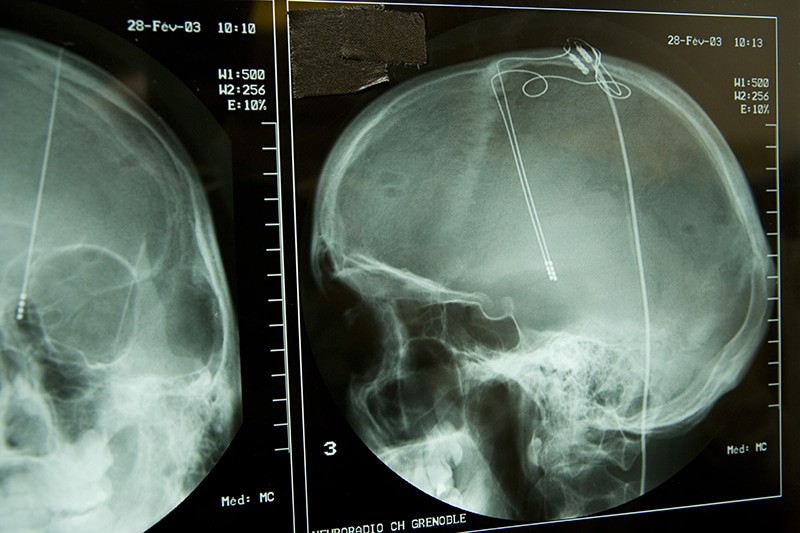

Deep Brain Stimulation (DBS) for OCD

NEWS: National Institute for Health and Care Excellence (NICE) say no to Deep Brain Stimulation. DBS for OCD Not Recommended Earlier today (28th April 2021) NICE published its interventional procedures guidance (IPG693) for the use of Deep Brain Stimulation (DBS) …

Deep Brain Stimulation for OCD – Your views

The National Institute for Health and Care Excellence (NICE) provides national guidance and advice to improve health and social care, and whose guidelines are used across the NHS. NICE are developing a new Interventional Procedures Guidance which looking at using …